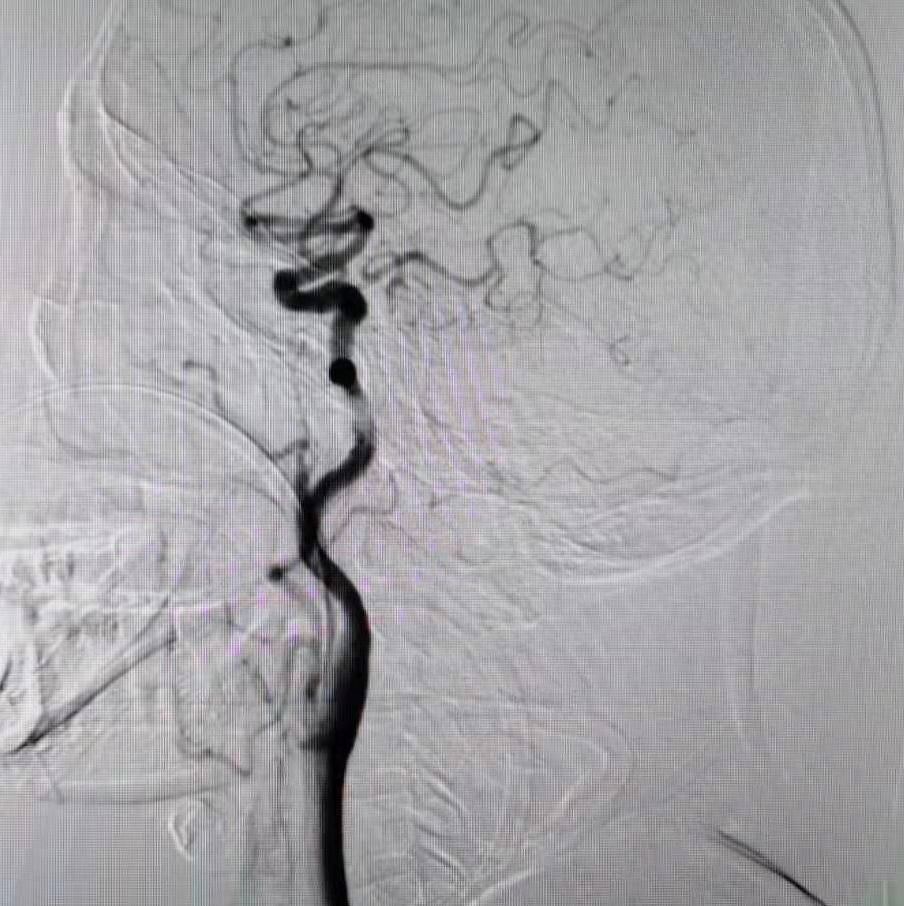

全脑血管造影提示右侧椎动脉颅内段闭塞,左侧椎动脉颅外段走形迂曲,基底动脉近端闭塞。

颈动脉造影示后交通开放。

5F 115cm远端通路导管超选至左侧椎动脉V2段,选取术中工作角度造影。

扩张后造影,提示恢复正向血流,残余狭窄50%左右。发现加奇SacSpeed® 2.5mm×9mm颅内球囊扩张部位存在双腔征,考虑血管夹层,给予替罗非班8ml/h持续泵入。

通过长交换技术,将XT-27定位在右侧大脑后动脉P2段,将Neuroform颅内支架3.5×15mm,定位在基底动脉狭窄处。

释放支架。